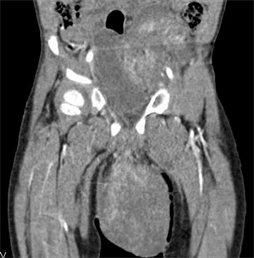

H.G. was a 30 months old boy admitted for the management of a testicular mass fortuitously discovered by the parents at the age of 6 months. It was then a small, painless and rapidly evolving testicular mass. A management had initially been started in a health facility, which consisted of a first excision of the mass that would have been total and a second one six months later as the mass recurred. An orchidectomy had not been performed. The anatomopathological investigation had found a proliferation of multinucleated cells of variable shape with eosinophilic cytoplasm; the desmin, actin and vimentin tests were positive. A pleiomorphic rhabdomyosarcoma had been concluded. He then received seven sessions of unsuitable and unsuccessful chemotherapy (Doxorubicin, Vincristine and Cyclophosphamid). Let’s mention that in the pediatric oncology unit, there was a not yet published cohort wherein the rhabdomyosarcoma proportion was 3.7% with 5 cases out of 132 children. H.G. was admitted at CHUMEL, two years after the disease onset in this context. No particular personal or family history was noted. The patient’s initial clinical examination revealed a general condition not significantly degraded, a normal skin and mucous membranes coloration, a good hydration and nutrition status with a weight of 11 kg. There was no infectious or edematous syndrome. The genitourinary examination revealed a shiny oval scrotal mass, 17 cm × 13 cm in size, a twisted and infiltrated penis, the presence of a left inguinal scar (Figure 1(a) and Figure 1(b)) and a bladder globe. The hepato-digestive examination revealed a fixed oval mass in the left iliac fossa, hard, painless with a regular surface, measuring 03 cm × 2.5 cm. There was no hepatomegaly or splenomegaly. The lymph nodes areas were free. The thoraco-abdominal scan performed as part of the extension investigation (Figure 2(a) and Figure 2(b)) revealed a large intra-scrotal mass measuring approximately 140 × 125 × 127 mm, having an heterogeneous multi-lobulated shape, a tissue (42 HU: Hounsfield Unity) and necrotic (30 HU) components, richly vascularized septa after contrast agent injection that persisted in the late stage; and a mass in the left iliac fossa with multi-lobulated shape, measuring 60 × 54 × 54 mm, heterogeneous, with a hyper-vascularized tissue and necrotic components, with an enhancement kinetics similar to the intra-scrotal mass, latero-deviating the bladder without invading it. No thoracic or bony location was observed. Proof-reading of the slide by another pathologist was consistent with the initial diagnosis of a pleiomorphic rhabdomyosarcoma. The tumor was classified as stage II (TNM) and had a poor prognosis (location, size, initial resection and

(a) (b)

Figure 2. Thoraco-abdominal CT scan ((a) transverse section of scrotal mass; (b) sagittal section).